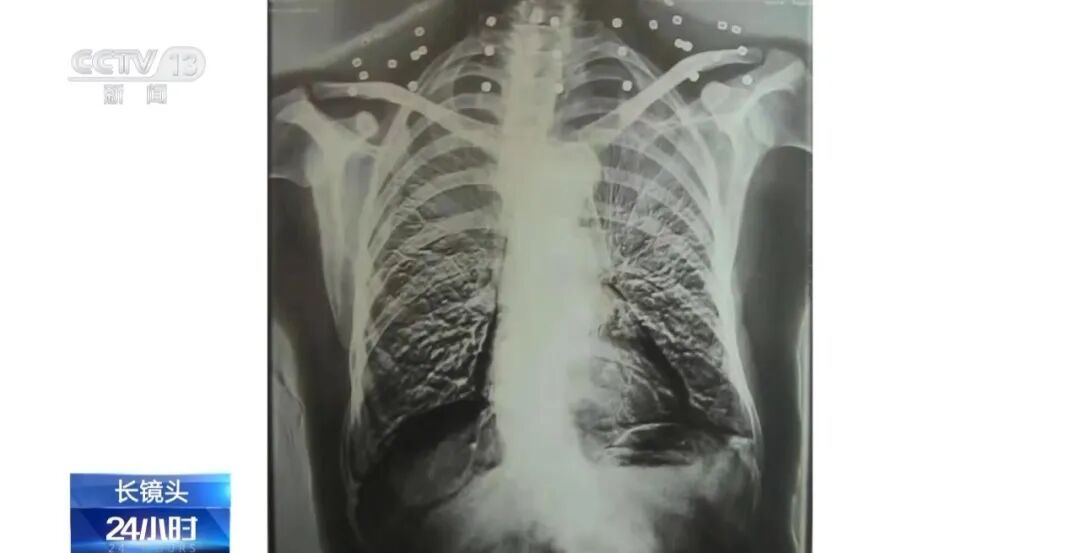

这张照片是82岁吴以贤的CT扫描。拍完照片后,医生说:“医生,请把项链摘下来再做CT。”

20年前,吴以贤做CT检查时,发现他的脖子上有很多碎片。医生认为这些碎片来自他所佩戴的项链,因此警告他将其取下并再次检查。

事实上,吴亦贤的脖子和腹部周围散落着总共33块碎片。

由33块组成的“项链”代表着军人的荣耀和英雄的真诚。